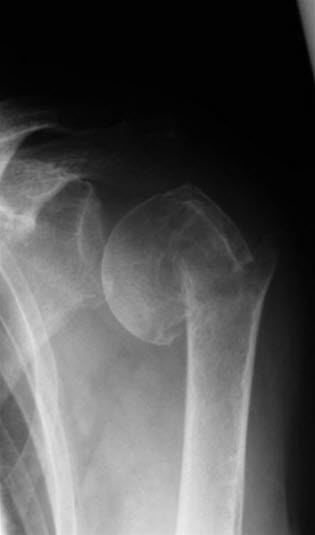

Tverrfraktur gjennom collum chirurgicum humeri med opprykking og lateralisering av skaftfragmentet